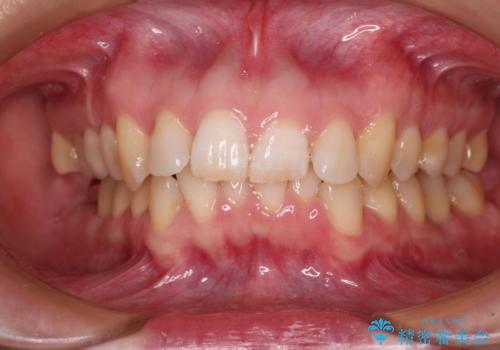

インビザライン単体で対応ることも検討できますが、達成する可能性が低いため、カリエールディスタライザーという補助装置を併用して、より確実性を上げることとしました。

奥歯の咬み合わせと深い咬み合わせを改善した後、インビザラインで歯列を整えることとしました。